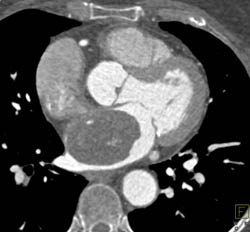

Fontan Shunt Not Opacified on Early Images in Patient With Single Ventricle